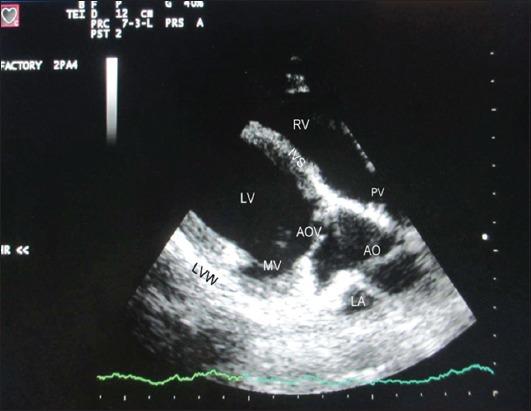

A total of 18, clinically healthy, adult Pantja goats of either sex, aged 2-4 years and weighing 10-44 kg were included in the study. Echocardiographic examination was performed in the standing unsedated animal. All measurements were made from the right parasternal long-axis left ventricular outflow tract view of the heart. The following parameters were recorded: Left ventricular internal diameter at diastole and systole, interventricular septal thickness at diastole and systole, left ventricular posterior wall (LVPW) thickness at diastole and systole, end diastolic and systolic volumes, stroke volume, fractional shortening, ejection fraction, percent systolic thickening of interventricular septum, percent systolic thickening of LVPW, cardiac output, left atrial (LA) diameter at diastole and systole, aortic (AO) root diameter at diastole and systole, LA/AO, LA posterior wall thickness at diastole and systole, left ventricular ejection time, DE amplitude, EF slope, AC interval and e-point to septal separation.

本研究共纳入18只2至4岁、体重10至44千克、临床健康的成年潘贾山羊,雌雄不限。在未使用镇静剂的站立动物身上进行超声心动图检查。所有测量均从心脏右胸骨旁长轴左心室流出道视图进行。记录以下参数:舒张末期和收缩末期左心室内径、舒张末期和收缩末期室间隔厚度、舒张末期和收缩末期左心室后壁(LVPW)厚度、舒张末期和收缩末期容积、每搏输出量、缩短分数、射血分数、室间隔收缩期增厚百分比、LVPW收缩期增厚百分比、心输出量、舒张末期和收缩末期左心房(LA)直径、舒张末期和收缩末期主动脉(AO)根部直径、LA/AO、舒张末期和收缩末期LA后壁厚度、左心室射血时间、DE幅度、EF斜率、AC间期以及e点至室间隔距离。